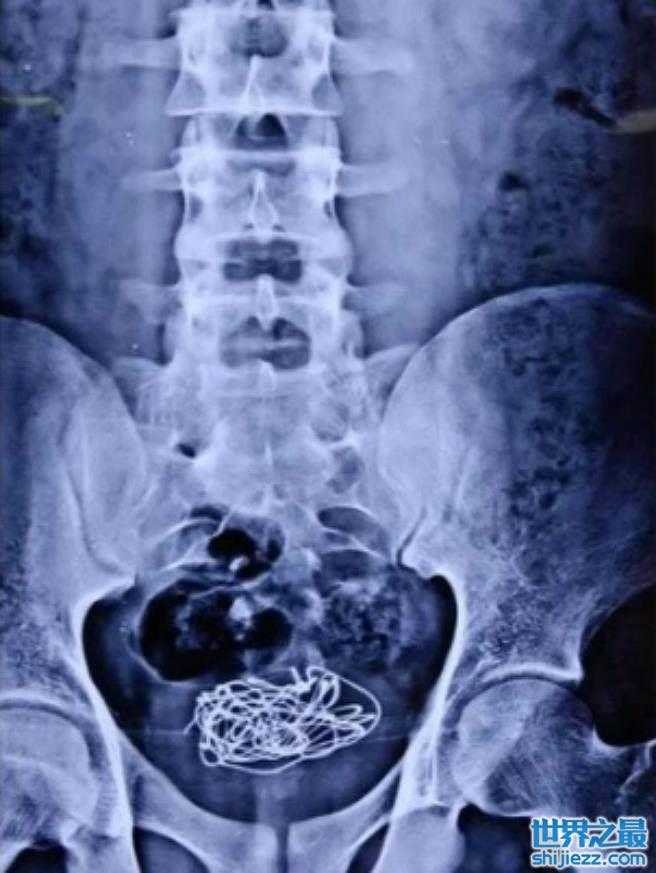

在印度曾经有一位男子因为腹部痛送到急诊室,没想到X光一照竟然发现里面有一团电线。在医生的逼问下,他才坦诚是之前为了助兴才塞进去的,没想到却卡在里面只好摆着,没想到却让自己变成排尿有困难。